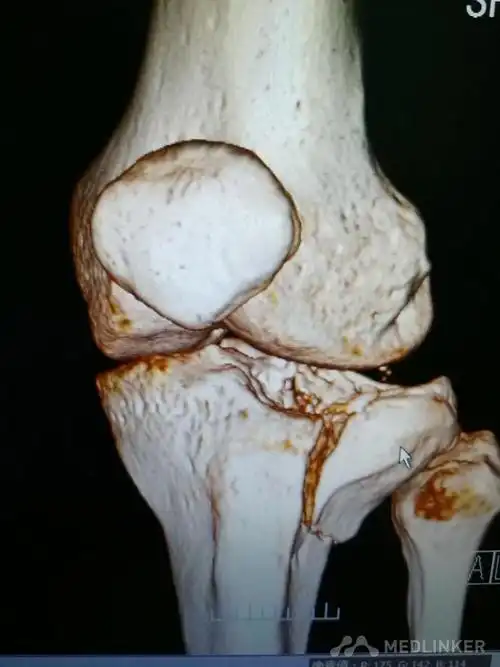

胫骨平台粉碎性骨折急会诊

复杂性胫骨平台骨折

一例复杂的胫骨平台骨折

复位不很完美的胫骨平台骨折

胫骨平台骨折的微创手术

胫骨平台骨折前外侧后外侧平台

胫骨平台骨折塌陷保守治疗